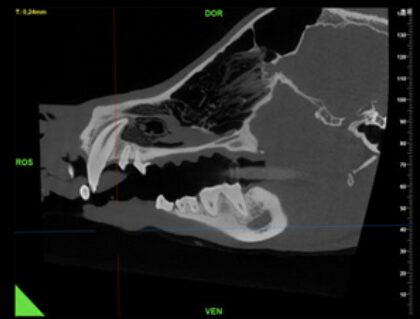

Dank neuester Technologien lassen sich sehr viele Erkrankungen der Zähne, des Kiefers und anliegender Strukturen, wie der Speicheldrüsen und Lymphknoten, detailgetreu und dreidimensional darstellen. Wo das herkömmliche Spiral-CT in der Detaildarstellung von Knochen und Zähnen an seine Grenzen kommt, fängt das Cone-beam CT erst an.